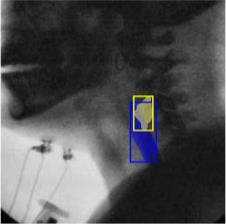

The videofluoroscopic swallowing study (VFSS) is a gold-standard imaging technique for assessing swallowing, but analysis and rating of VFSS recordings is time consuming and requires specialized training and expertise. Researchers have recently demonstrated that it is possible to automatically detect the pharyngeal phase of swallowing and to localize the bolus in VFSS recordings via computer vision, fostering the development of novel techniques for automatic VFSS analysis. However, training of algorithms to perform these tasks requires large amounts of annotated data that are seldom available. We demonstrate that the challenges of pharyngeal phase detection and bolus localization can be solved together using a single approach. We propose a deep-learning framework that jointly tackles pharyngeal phase detection and bolus localization in a weakly-supervised manner, requiring only the initial and final frames of the pharyngeal phase as ground truth annotations for the training. Our approach stems from the observation that bolus presence in the pharynx is the most prominent visual feature upon which to infer whether individual VFSS frames belong to the pharyngeal phase. We conducted extensive experiments with multiple convolutional neural networks (CNNs) on a dataset of 1245 bolus-level clips from 59 healthy subjects. We demonstrated that the pharyngeal phase can be detected with an F1-score higher than 0.9. Moreover, by processing the class activation maps of the CNNs, we were able to localize the bolus with promising results, obtaining correlations with ground truth trajectories higher than 0.9, without any manual annotations of bolus location used for training purposes. Once validated on a larger sample of participants with swallowing disorders, our framework will pave the way for the development of intelligent tools for VFSS analysis to support clinicians in swallowing assessment.